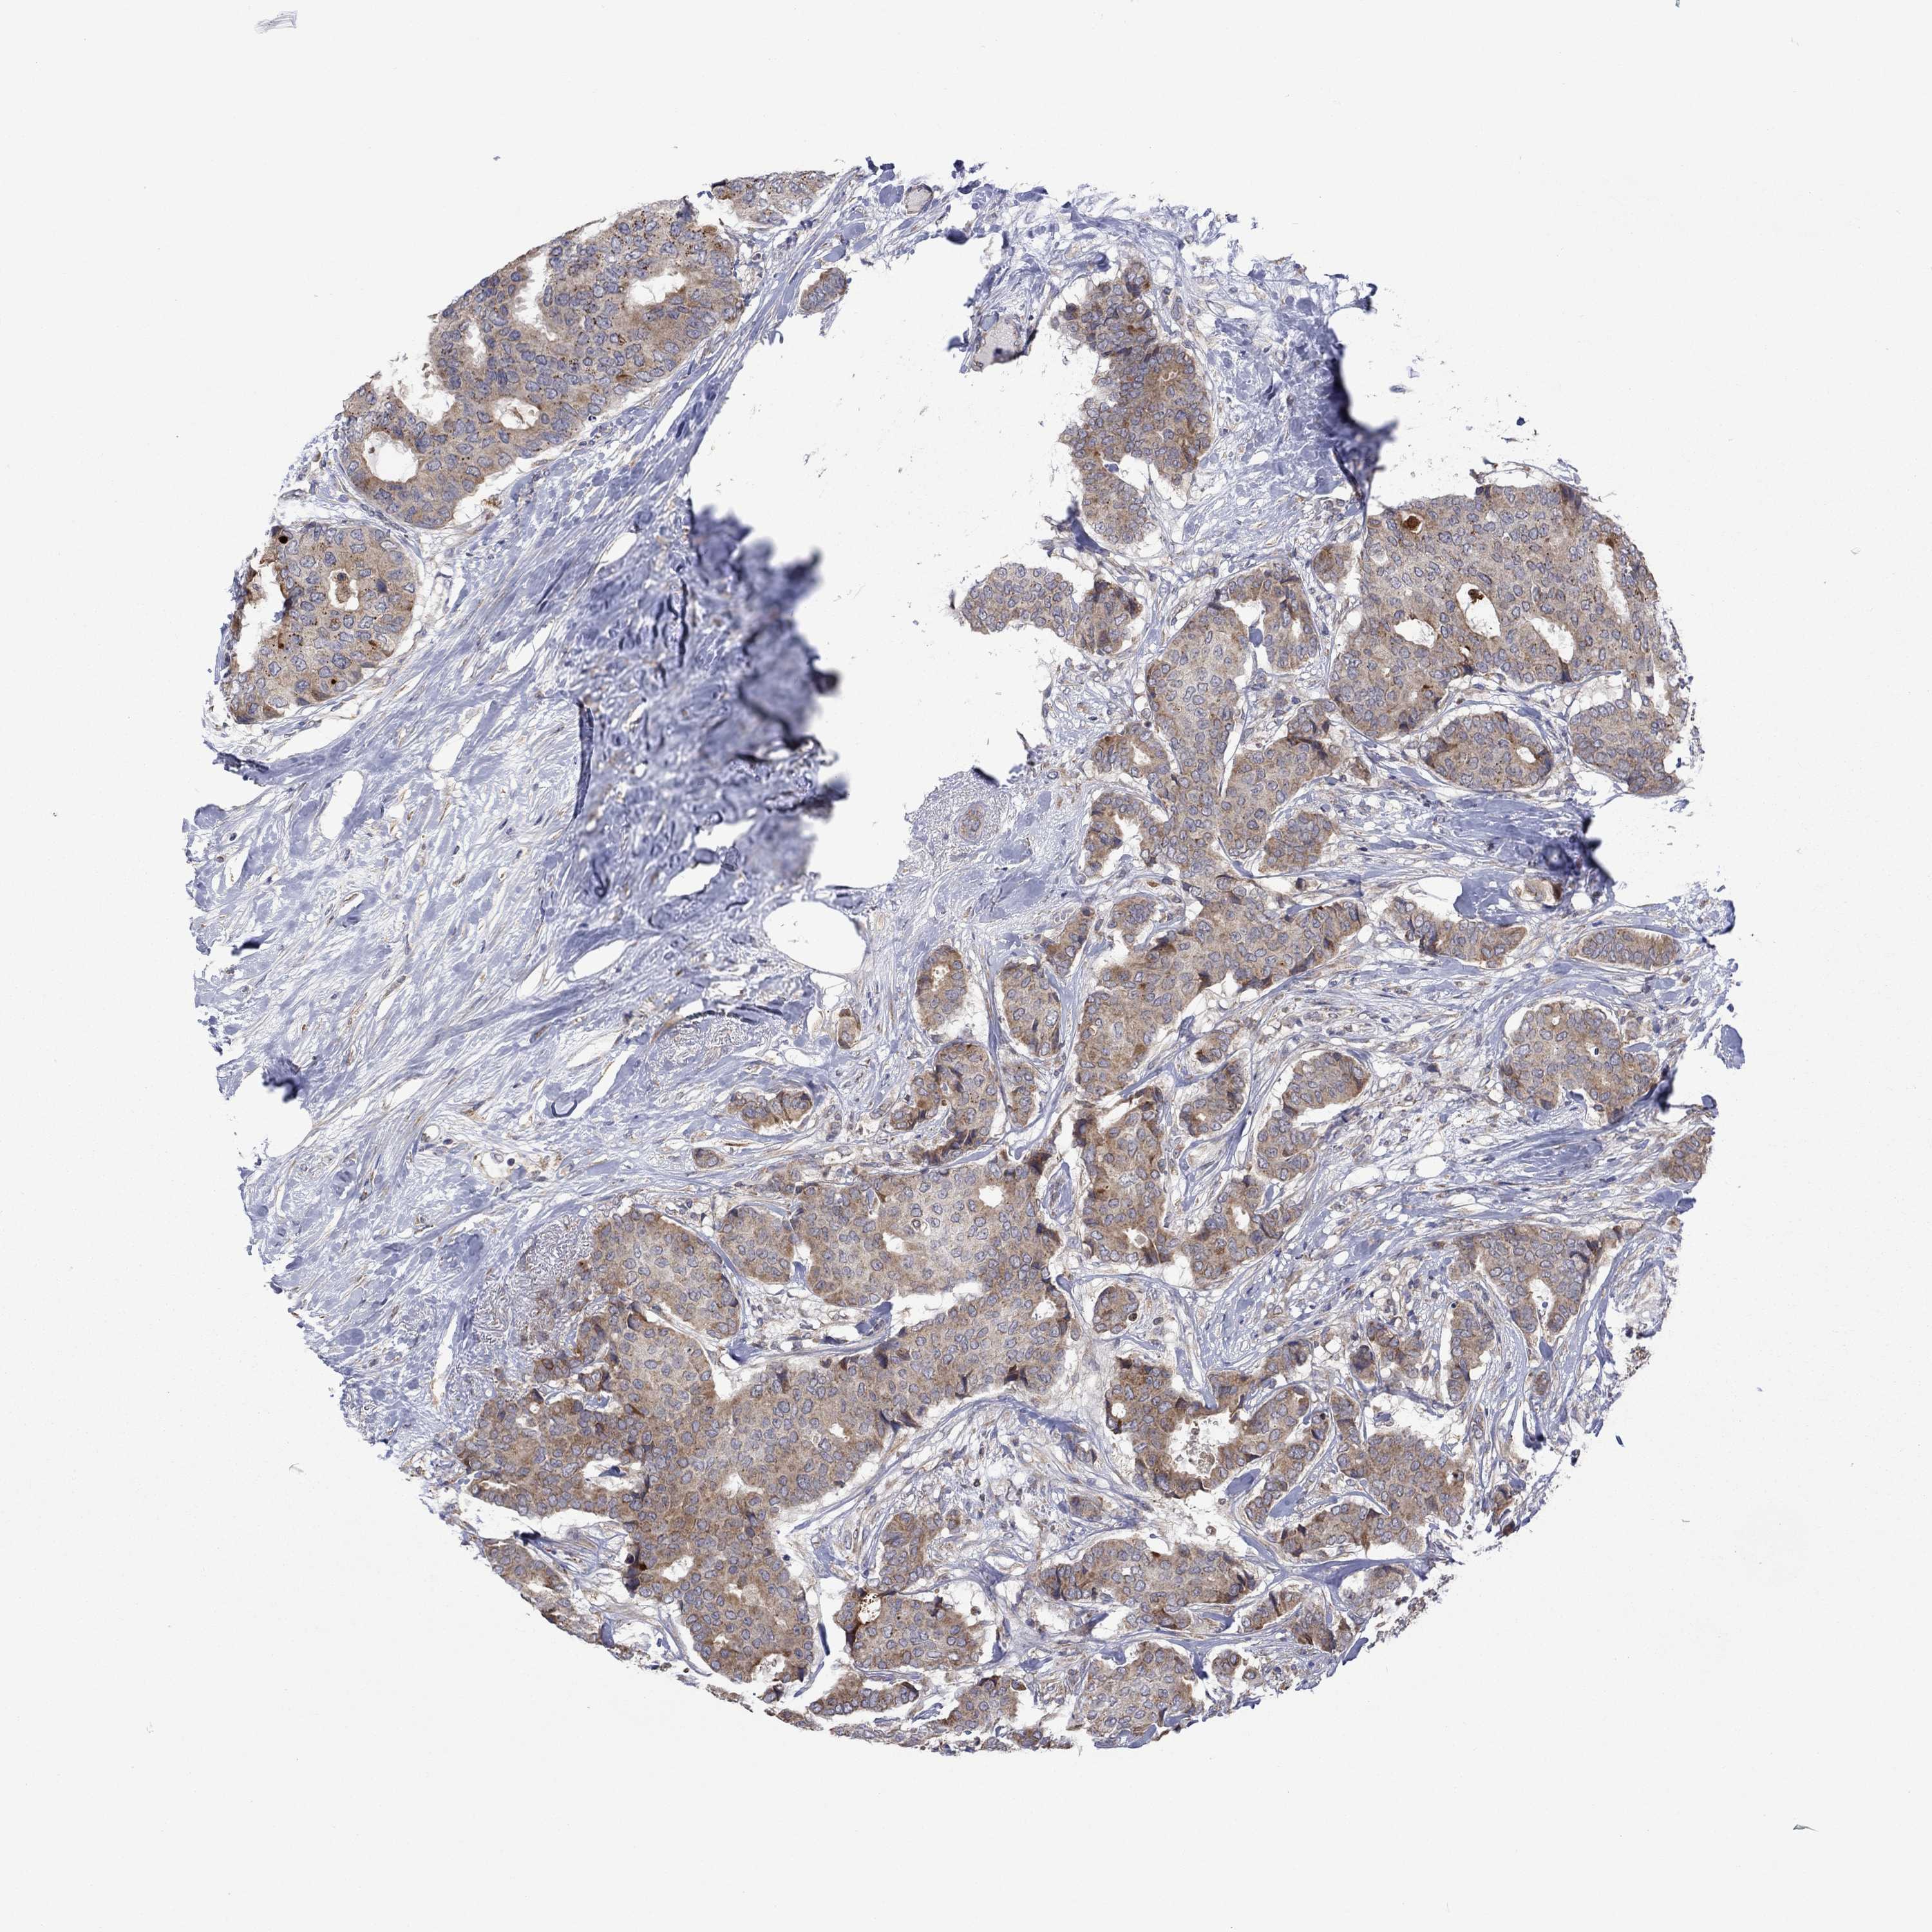

CANCER BREAST CANCER Show tissue menu

BRCA TCGA BRCA VALIDATION PROTEIN EXPRESSION

ANTIBODIES

AND

VALIDATION